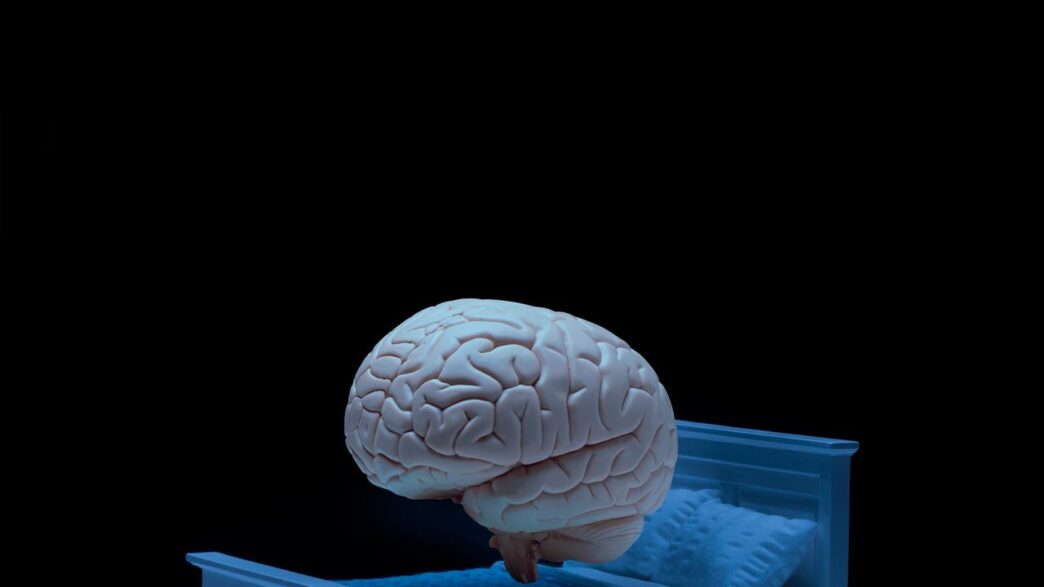

Aunque la relación entre la falta de sueño y la demencia se conoce desde hace tiempo, no estaba claro si los malos hábitos de sueño podían causar demencia o si, por el contrario, la falta de sueño era un síntoma temprano de esta enfermedad. Sin embargo, nuevas investigaciones han revelado que la calidad del sueño puede tener un impacto directo en el ritmo de envejecimiento cerebral.

«Hay evidencia de que la falta de sueño puede acelerar el envejecimiento cerebral, y una de las formas en que esto sucede es a través de la inflamación», explica Abigail Dove, neuroepidemióloga del Instituto Karolinska en Suecia.

Qué dice el estudio

Los investigadores evaluaron la calidad del sueño en cinco dimensiones en 27,500 personas de mediana edad y mayores, con una edad promedio de 54.7 años, inscritas en el Biobanco del Reino Unido, un instituto de investigación que realiza estudios de seguimiento a largo plazo sobre los efectos de la predisposición genética y el estilo de vida en las enfermedades. Aproximadamente nueve años después, escanearon los cerebros de los participantes mediante resonancia magnética y utilizaron modelos de aprendizaje automático para estimar su edad cerebral biológica.

La calidad del sueño se cuantificó según cinco factores: cronotipo (matutino o vespertino), duración del sueño, presencia o ausencia de insomnio, presencia o ausencia de ronquidos y somnolencia diurna. Con estos datos, clasificaron a los participantes en tres patrones de sueño y encontraron que el 41.2% tenía un sueño saludable, el 3.3% un sueño claramente deficiente y el 55.6% se encontraba en el grupo intermedio.

El análisis mostró que, por cada punto de disminución en la puntuación de sueño saludable, la diferencia entre la edad cerebral y la edad cronológica aumentaba aproximadamente seis meses. El grupo con peor calidad de sueño presentó cerebros aproximadamente un año mayores que su edad cronológica. Esto sugiere que las diferencias en la duración y los hábitos de sueño pueden afectar significativamente el ritmo de envejecimiento cerebral.

Los investigadores también descubrieron que un estilo de vida nocturno, una duración de sueño inadecuada (más o menos de 7-8 horas) y los ronquidos están fuertemente asociados con el envejecimiento cerebral. Además, observaron que los cinco factores que determinan la calidad del sueño interactúan entre sí. Por ejemplo, el insomnio puede provocar somnolencia diurna excesiva, y un estilo de vida nocturno puede reducir las horas de sueño.